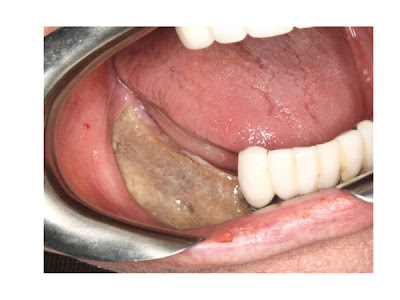

A osteonecrose implica na perda da vascularização óssea em pacientes submetidos a tratamentos a base de medicamentos como os bisfosfonatos, sendo desencadeada por procedimentos rotineiros como exodontias, cirurgias envolvendo tecido ósseo ou até mesmo em pacientes sem histórico de intervenção nessas regiões. Ocorre a exposição de tecido necrótico por no mínimo 8 semanas sem que tenha havido irradiação prévia da região. Outros eventos desencadeantes podem ser a confecção de próteses mal adaptadas que acabam lacerando a mucosa, doença periodontal, úlceras traumáticas, traumas maxilofaciais, abcessos dentais, entre outros.

O diagnóstico clínico pode ser feito pela presença de fístula em áreas sem histórico de intervenção prévia, assim como relatos de dor na região, sendo confirmado através de exames radiográficos e tomográficos, onde é possível verificar a perda de estrutura óssea de maneira difusa ou até mesmo áreas de sequestro ósseo.

- Estágio 1: Osteonecrose com exposição, assintomático e sem sinais de infecção.

- Estágio 2: Osteonecrose com exposição, em pacientes com sinais clínicos de infecção.

- Estágio 3: Osteonecrose com infecção e presença de fratura patológica, fístula extra-oral ou osteólise/seqüestros ósseos.